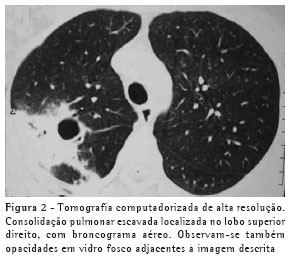

RESULTADOSO achado de imagem mais freqüente, presente nos 7 pacientes, foi consolidação de contornos mal definidos (Figuras 1, 2, 3 e 4), sendo que 5 deles tinham broncograma aéreo de permeio, principalmente na periferia da lesão. Em 3 casos, a consolidação organizava-se sob forma de massa. Em 6 dos 7 pacientes foram observadas, no interior das consolidações, áreas irregulares de escavação, múltiplas em 5 e única em 1 paciente. Em um dos casos não se observou escavação, mas ele mostrava áreas hipodensas de permeio, sugestivas de necrose (Figura 5). Apenas um dos pacientes apresentou nível líquido no interior das cavidades.

A lesão escavada predominou nos lobos superiores, sendo 4 à direita e 1 à esquerda. Em um destes pacientes, ela acometia também o lobo médio. Em 2 casos, ela ocorreu nos lobos inferiores, 1 à direita e 1 à esquerda. Em 4 casos as lesões acometiam apenas os lobos citados, sendo portanto unilaterais. Nos outros 3, atingiam também, em menor intensidade, o pulmão contralateral. Em um caso, havia também escavação de paredes relativamente finas, multisseptada, sem nível líquido, localizada no lobo médio.

Opacidades em vidro fosco foram vistas em 6 pacientes, localizadas predominantemente ao redor das lesões escavadas, não sendo, em nenhum dos casos, achado predominante.

Na nossa casuística, o principal padrão de acometimento pulmonar foi o de consolidação com broncograma aéreo de permeio e escavação, presente em 6 pacientes, sendo as escavações múltiplas em 5 casos e única em 1. As consolidações tinham grandes proporções e contornos anfractuosos. Os broncogramas aéreos estavam localizados nas porções periféricas das lesões. O lobo pulmonar mais freqüentemente envolvido foi o lobo superior direito, acometido em 4 pacientes. A maioria dos trabalhos de revisão de casos confirma tais achados.(2,5) Alguns trabalhos relatam que, embora a escavação possa não estar presente no momento do diagnóstico, ela acaba por se desenvolver durante a evolução da doença.(4) Níveis líquidos no interior das escavações foram vistos em apenas um paciente na casuística estudada.

Outros achados foram as opacidades em vidro fosco, os nódulos do espaço aéreo, os pequenos nódulos de distribuição predominantemente centrolobular, e o padrão de árvore em brotamento. Eles se localizavam predominantemente ao redor das consolidações escavadas, sendo que em um dos casos também estavam presentes em ambos os lobos inferiores. Acredita-se que tal achado deva representar disseminação broncogênica da infecção.